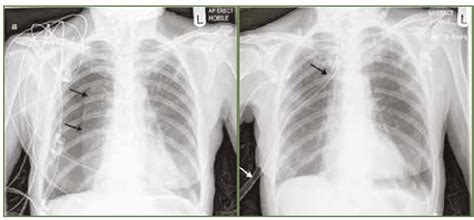

Diagnostický proces sa začína dôkladnou anamnézou. Zisťujeme dĺžku trvania kašľa, možné spúšťače, prípadný kontakt so znečisteným vzduchom a zmeny v okolí. Počas klinického vyšetrenia sa zameriavame na posluch hrudníka, pričom často detegujeme chrípky a predĺžený výdych. RTG snímky hrudníka odhalia bronchointersticiálny vzor, zhrubnutie stien priedušiek a občas aj hyperinfláciu. V prípade astmatu je patrné výraznejšie bronchiálne zobrazenie, zatiaľ čo pri pneumónii sú viditeľné skôr konsolidácie. Na posúdenie stavu sliznice a získanie vzoriek sa uchyľujeme k bronchoskopii. V jej rámci sa odoberá bronchoalveolárna laváž, na základe ktorej sa vykoná cytologická analýza BAL a kultivácia. Diagnostický obraz dopĺňajú krvné testy. Zahŕňajú kompletný krvný obraz, biochemický profil a u starších jedincov testy štítnej žľazy. Pri problémoch s dýchaním cez ústa alebo pri podozrení na pľúcne edémy sa sústreďujeme na vylúčenie srdcových príčin prostredníctvom NT-proBNP testu a echokardiografie. V rámci kompletného vyšetrenia neopomíname ani testy na pľúcne parazity. Používajú sa Baermannova metóda, flotácia a v prípade potreby PCR test na zistenie Aelurostrongylus.